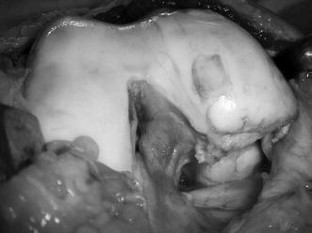

Nonunion of a Hoffa fracture in an adult

The coronal fractures of femoral condyles, known as Hoffa fractures, are a rarity. Conservative management often leads to unsatisfactory results and nonunion. In this study, we present a case of a 35-year-old patient with an established nonunion of medial Hoffa fracture of right knee treated with open reduction and internal fixation.

Fig. 3